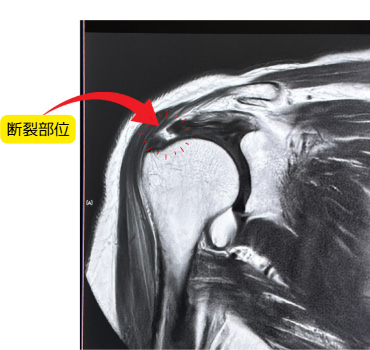

腱板断裂(けんばんだんれつ)

肩を支える「腱板」と呼ばれる筋肉・腱の一部が、加齢や外傷などで部分的または完全に切れてしまう状態です。

転倒や重い荷物を持ち上げた際に発症することもあります。

放置すると肩の機能が低下し、日常生活に支障が出ることもあります。

MRIで断裂の有無や程度を確認します。